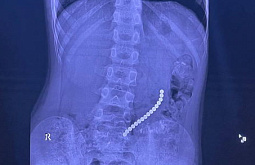

В Улан-Удэ осмотрели детей с тяжёлыми деформациями позвоночника и грудной клетки

Здоровье, 24.02.2025 10:01

15 детей направят в Санкт-Петербург для оперативного лечения